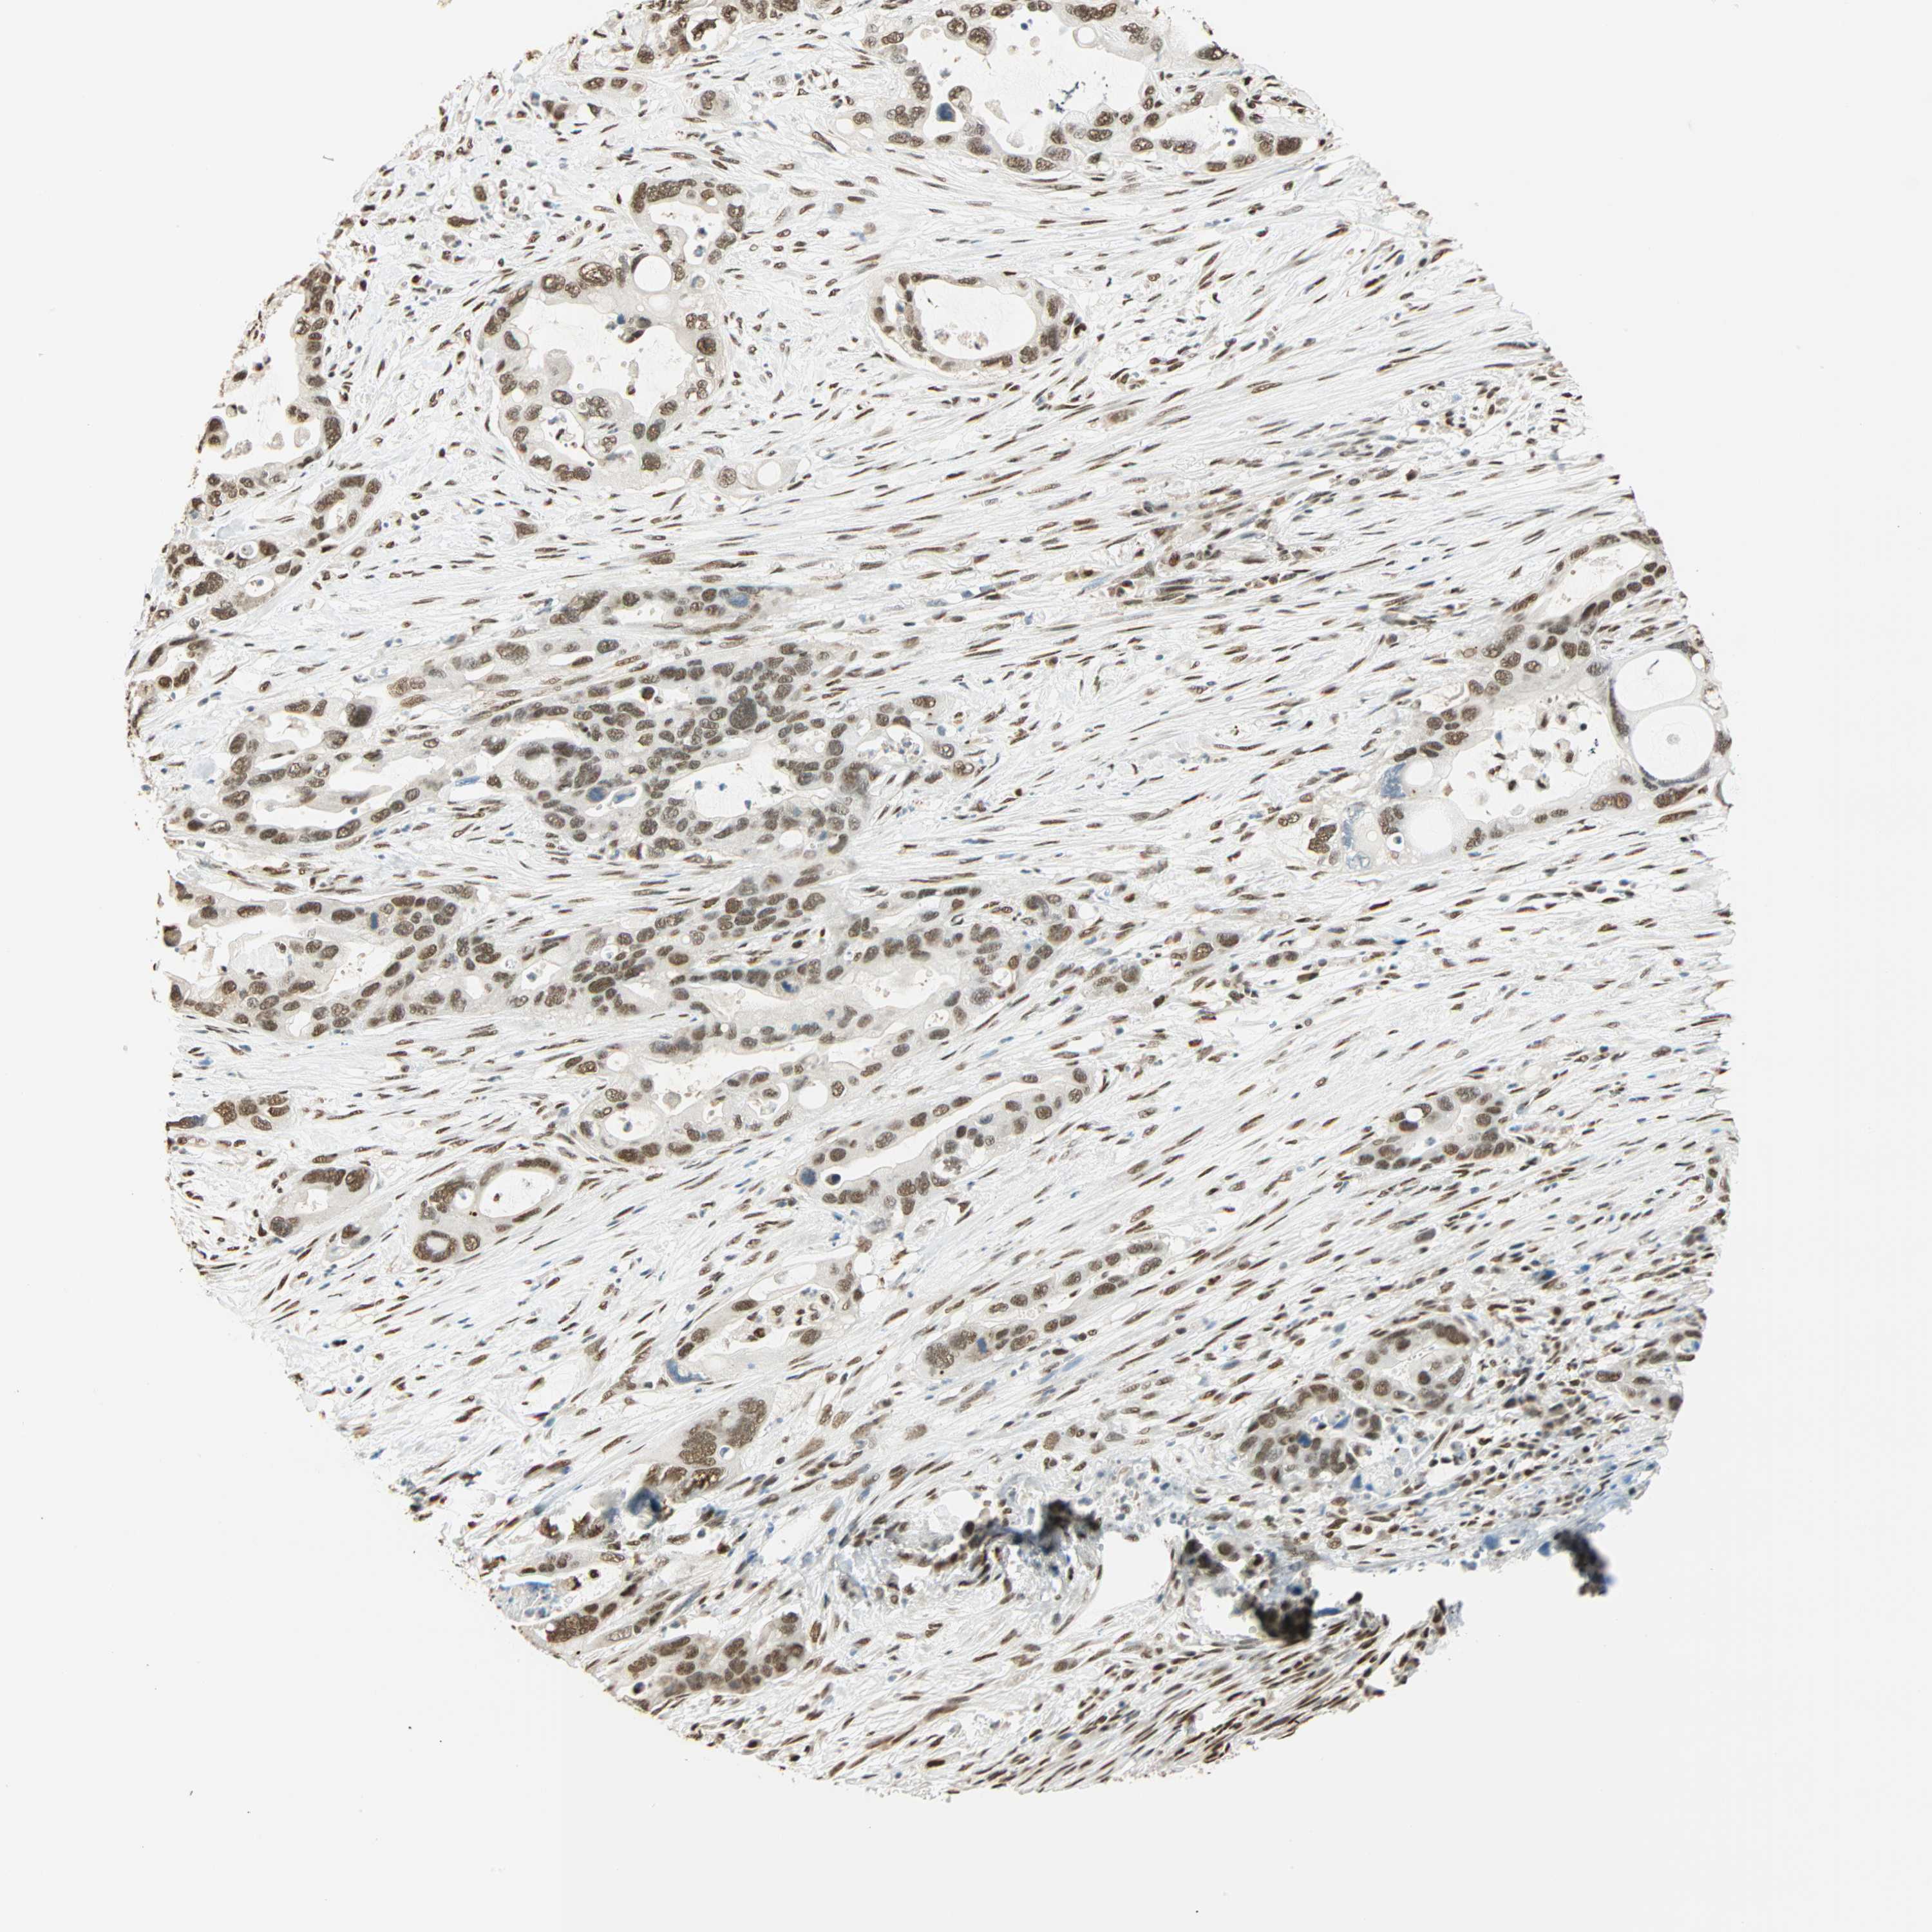

PANCREATIC CANCER - Protein expressioni

A mouse-over function shows sample information and annotation data. Click on an image to view it in a full screen mode. Samples can be filtered based on level of antibody staining by selecting one or several of the following categories: high, medium, low and not detected. The assay and annotation is described here.

Note that samples used for immunohistochemistry by the Human Protein Atlas do not correspond to samples in the TCGA dataset.

Antibody stainingi

Antibody staining in the annotated cell types in the current human tissue is reported as not detected, low, medium, or high, based on conventional immunohistochemistry profiling in selected tissues. This score is based on the combination of the staining intensity and fraction of stained cells.

Each image is clickable and will lead to virtual microscopy that enables deeper exploration of all samples and also displays staining intensity scores, fraction scores and subcellular localization as well as patient and tissue information for each sample.

Antibody CAB008105

Staining

High

Medium

Low

Not detected

Intensity

Strong

Moderate

Weak

Negative

Quantity

>75%

75%-25%

<25%

None

Location

Nuclear

Cytoplasmic/membranous

Cytoplasmic/membranous,nuclear

Adenocarcinoma, NOS

Adenocarcinoma, metastatic, NOS